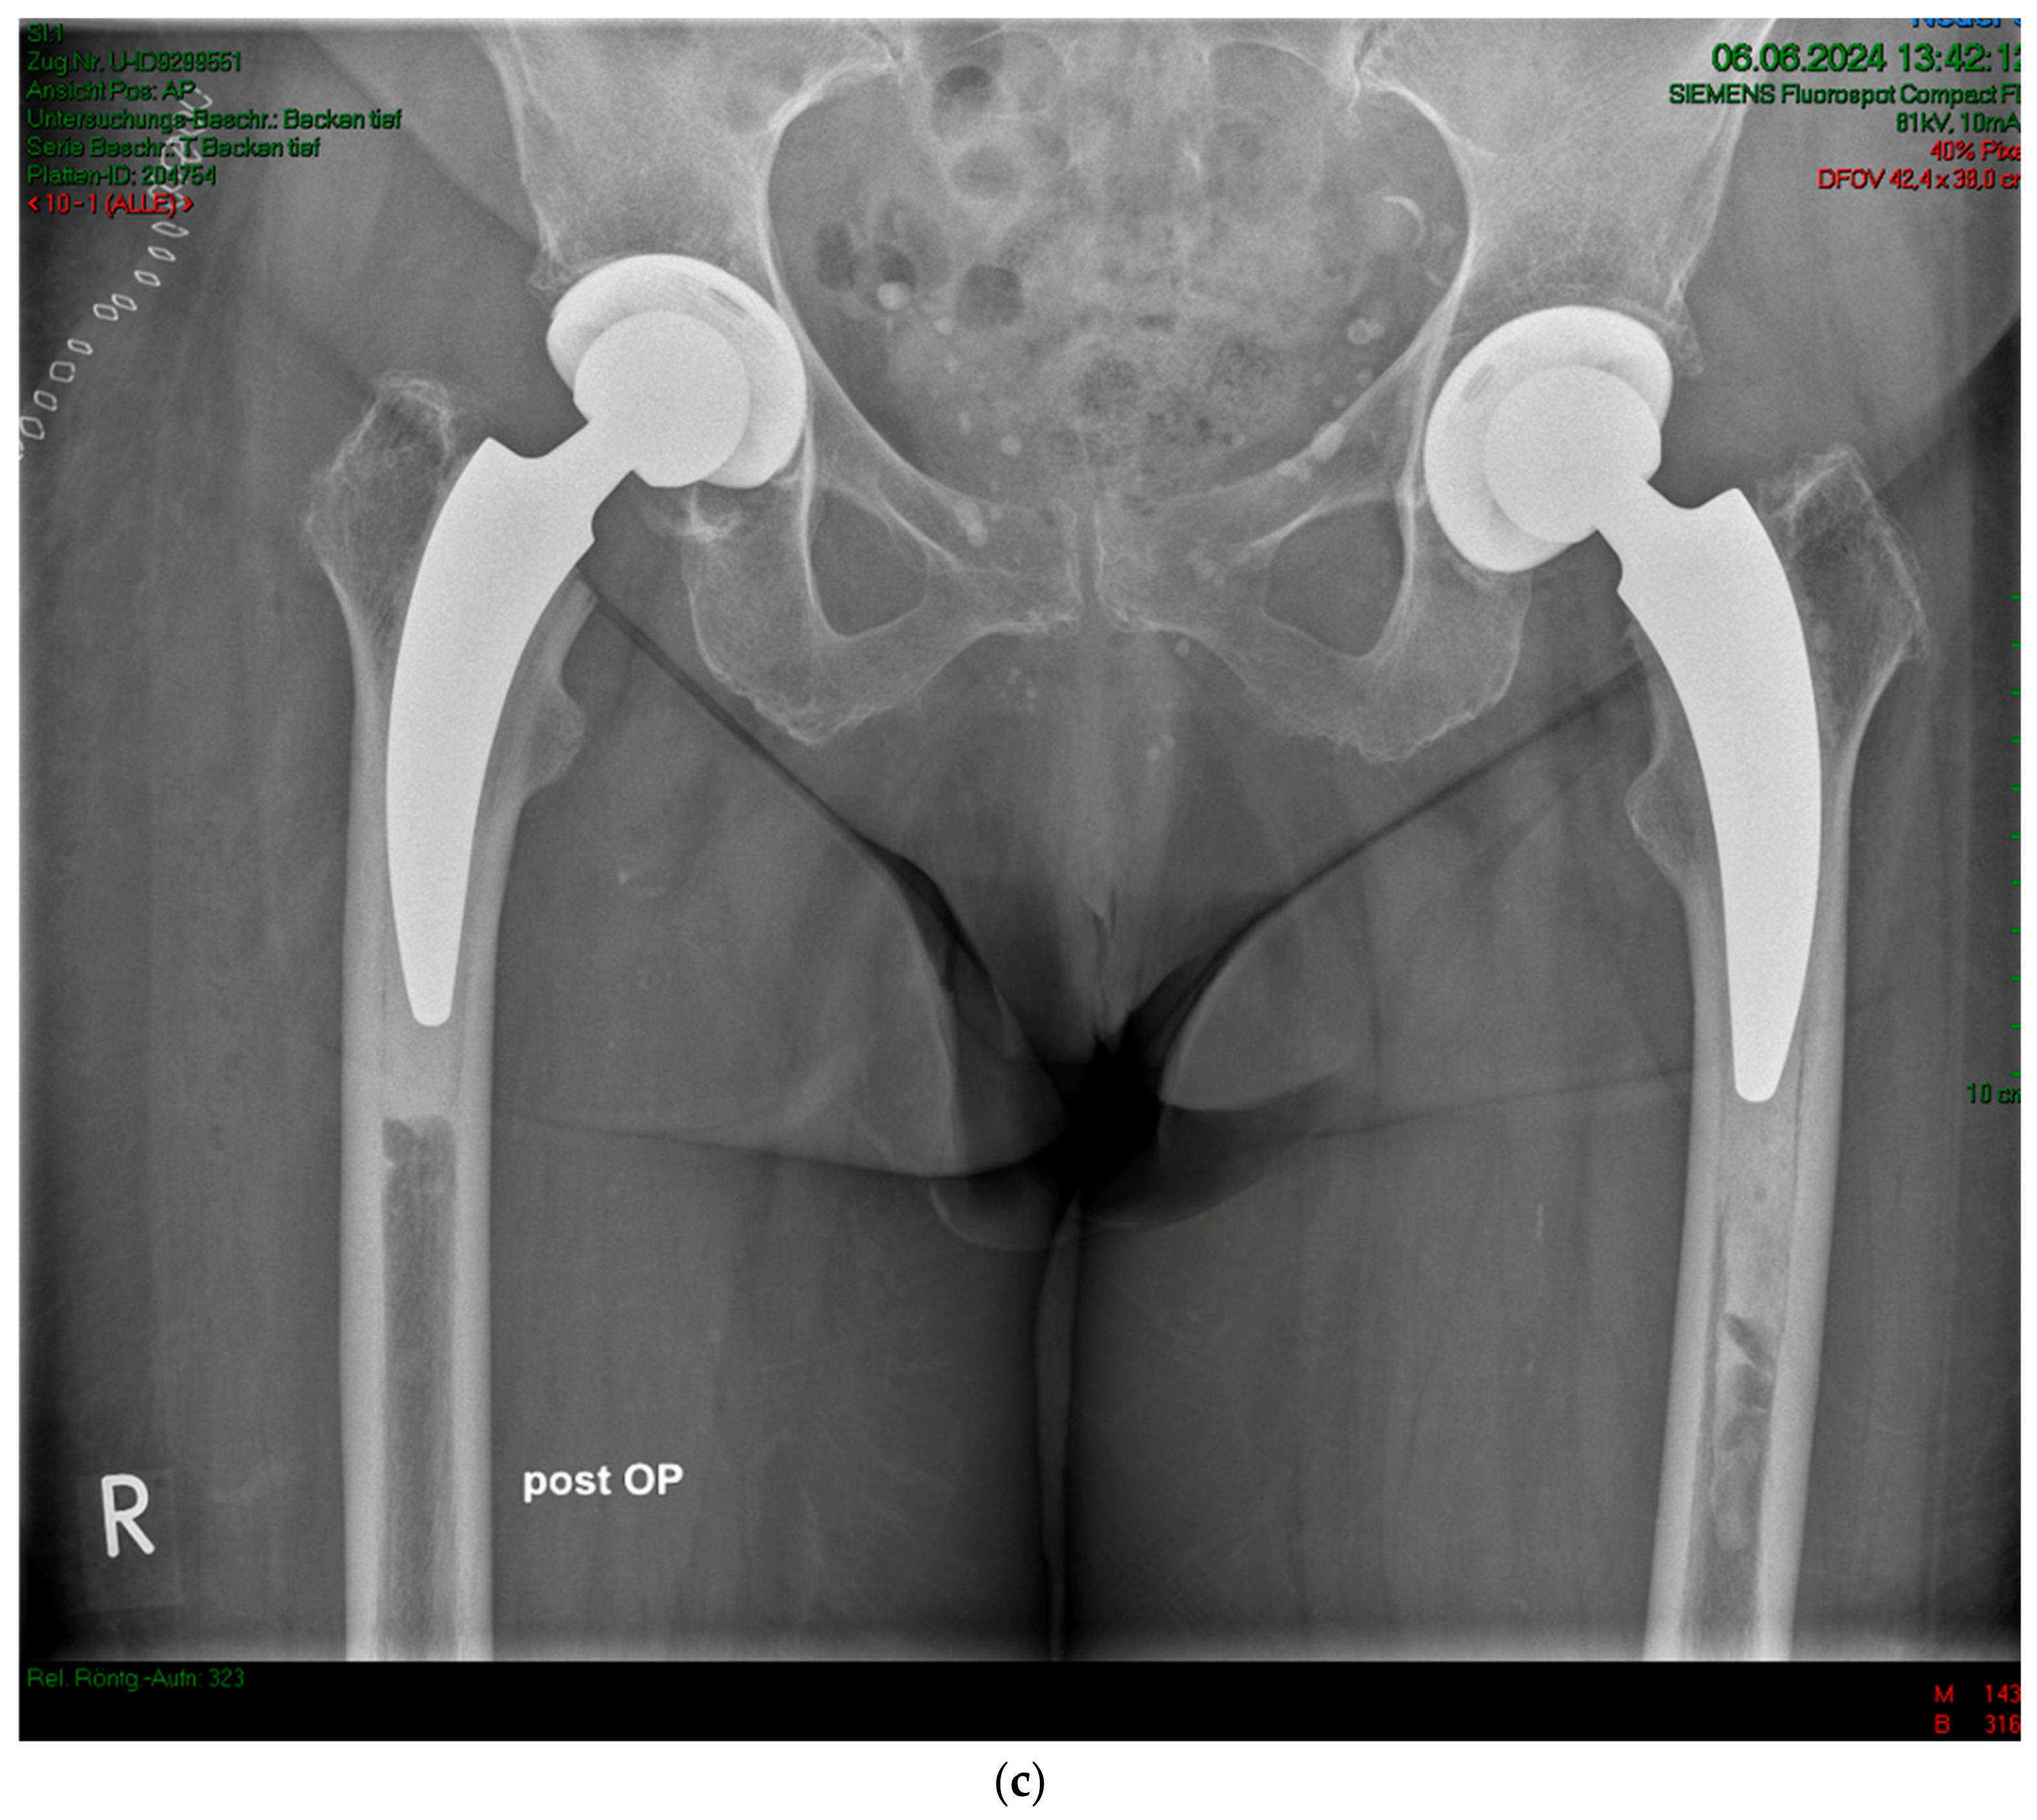

2. Materials and Methods